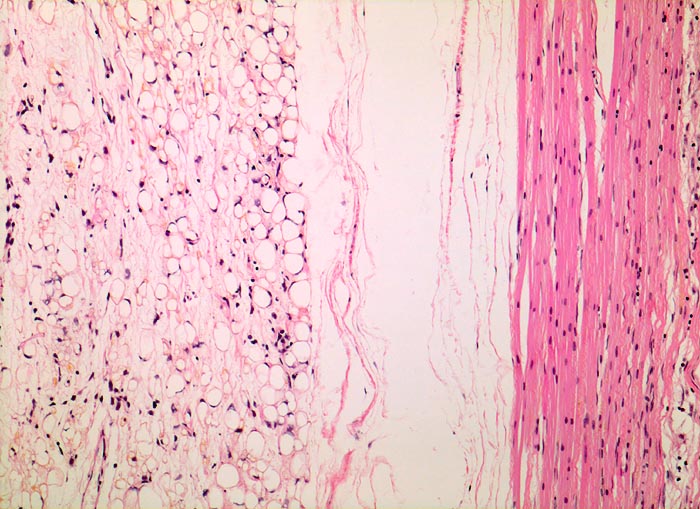

myxoides Liposarkom

Muskel, untere Extremität

Rechts im Bild komprimierte atrophe Skelettmuskulatur. Links davon die peripheren Anteile des Sarkoms mit zahlreichen Lipoblasten, die in der Übersicht an reifes Fettgewebe erinnern.

Schmerzloser Tumor am medialen Oberschenkel.

Histologie

100